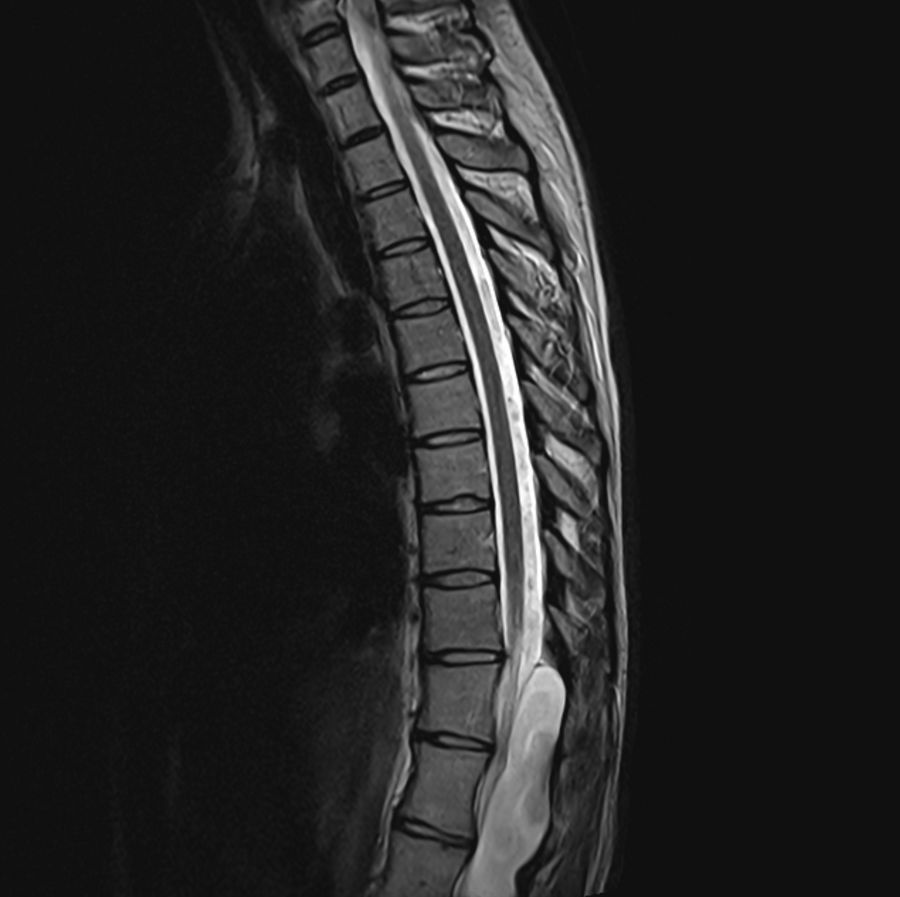

Kaitlin had an arachnoid cyst, meaning it wasn’t cancerous or malignant. It was, however, compressing her spinal cord, causing her chronic pain and leaving her unable to activate muscles.

Spinal cysts are rare and Kaitlin’s was located at her thoracolumbar junction — the mid-back region where the thoracic spine meets the lumbar spine — making it even more atypical.

Spine image